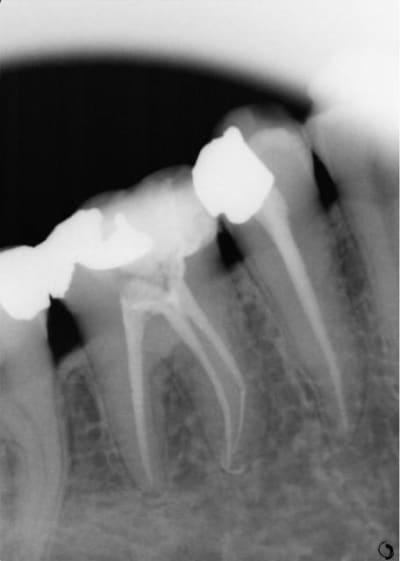

Allez pour parler un peu du quotidien, un cas d'endo qui date d'un petit moment, que feriez vous ?

Ca a été fait sous digue et c'est du niti pur sucre en ML...

Onlay ou couronne (impossible de dire sans évaluer les pertes de substances exactes, ce que ne permet pas la retro).

les obturation endo 'french touch' à la lime cassée , sont vraiment ce qui se fait de mieux.. regarde, l'image radio est sur l'obturation à la gutta...

on semble voir sur le distal un début de lésion. peut être que malgré ton geste plutôt bien réalisé l'irrigation n'aie pas été suffisante. SI tu avais un débût de nécrose.

POur ton ni ti il semble qu'il y aie une sortie commune donc pas de souci.

La première radio du post était de 2006, c'était une bio classique, pas de nécrose, grosse carie juxta pulpaire.